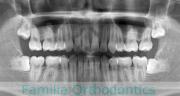

No.22V-029

- 叢生

- 上顎前突

- 19歳

- 男性

- 抜歯部位

- 上:

- 8448

- 下:

- 主な使用装置:

- FEA 022

- 治療にかかった費用:

- 92万円

でこぼこを治したいということで来院されました。上下左右から親知らずも第一小臼歯も抜歯が必要で、歯科矯正アンカースクリューを併用して大臼歯を後ろに引っ張りながらの治療でした。3年弱、35回程度の通院が必要でした。

叢生が著しく、後戻りのリスクがあります。またアンカースクリューが必須のため、もしもスクリューが安定しないと、治療が難しく長くなってしまう恐れがありましたが、幸い脱落は見られませんでした。